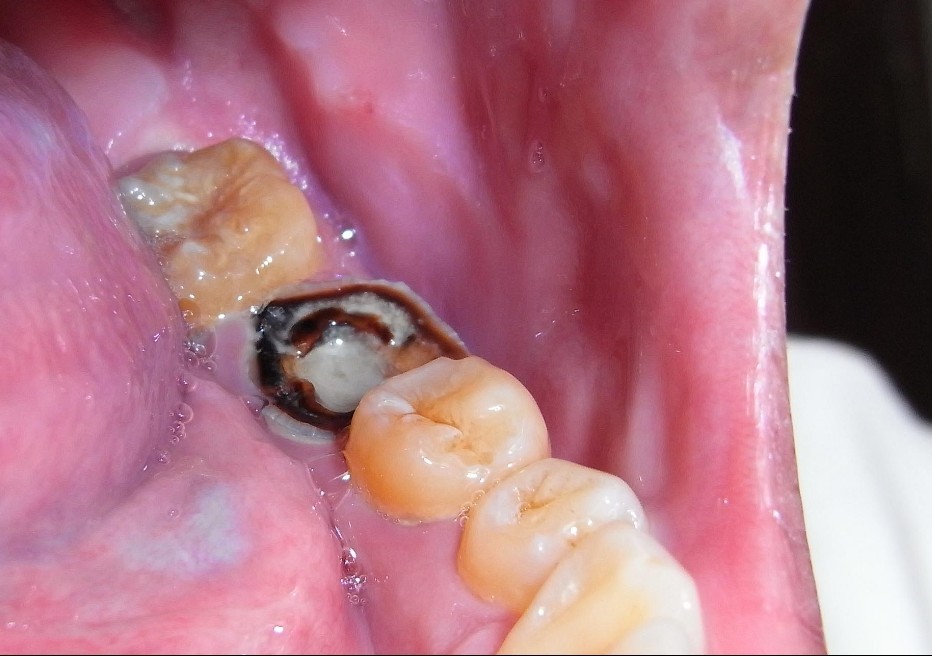

蛀牙侵蚀牙齿使得牙齿受损形成牙洞,当蛀牙危及到牙龈,就会导致牙齿疼痛。其实,不同的蛀牙种类引起的症状也不一样。下面请看康贝佳口腔医生为您介绍蛀牙的种类。

大连康贝佳口腔医生表示:蛀牙是非常严重的问题。如果置之不理,蛀牙能破坏牙齿并破坏牙齿的中央神经,从而导致脓肿,也就是牙根顶端的局部感染。一旦脓肿形成,只能通过牙根管疗法、外科手术或拔除牙齿进行治疗。蛀牙的种类具体分为以下两种:

1、冠状蛀牙

是比较普遍的类型,儿童和成人都可能患,冠状蛀牙通常位于牙齿的咀嚼面或牙齿之间。

2、根部蛀牙

随着年龄增长,牙龈开始衰退,部分牙根就会暴露在外。牙根失去牙釉质的保护,暴露在外的部位就容易受蛀。多发性蛀牙通常在填料和牙冠周围出现。这些部位容易积聚牙渍,从而导致蛀牙。>>>根管治疗疼不疼?在线咨询<<<